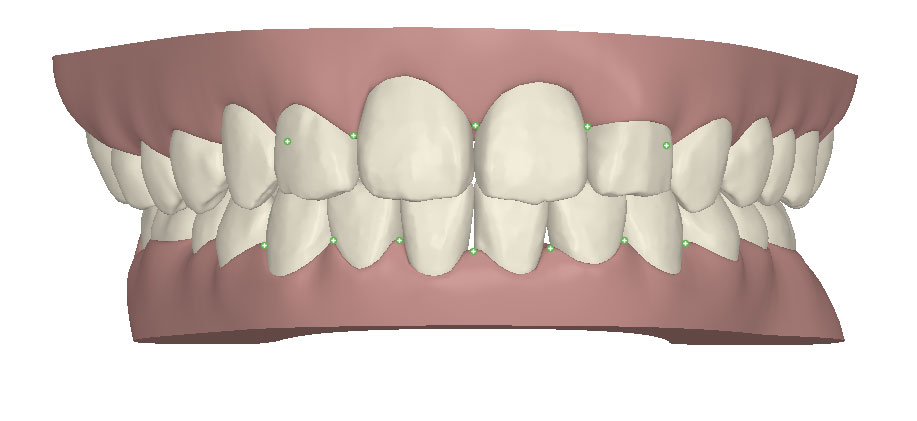

コンピューターを使って作製した透明なマウスピース型の矯正装置(アライナー)を段階的につけ替えていき、それにより歯列を矯正し、歯並びへと改善します。はじめに 治療開始から終了までのアライナーができあがってきます。マウスピース型矯正装置(インビザライン)の最大の特徴として「クリンチェック」というソフトがあります。3D のコンピュータ シュミレーション画像で、治療開始から完了までを目で見て確認することができます。

マウスピース型矯正装置(インビザライン)治療においては、クリンチェックというシミュレーションソフトを活用しております。

このクリンチェックの魅力は、治療前の現在の歯並びから治療後の歯並びを視覚化して患者様にご説明できる点にあります。

また、抜歯・非抜歯、全体矯正・部分矯正などそれぞれの治療パターンをシミュレーションすることが可能です。